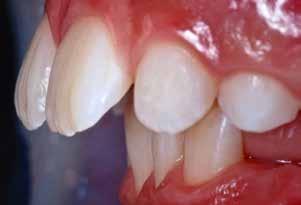

B.M. Bambina di sei anni e mezzo, con malocclusione scheletrica di II Classe, deep-bite over-jet elevato, lieve contrazione dell’arcata superiore, alterazione dell’eruzione dell’elemento dentale 21.

Fig. 123 > Immagine intraorale laterale destra.

Fig. 124 > Immagine intraorale laterale sinistra.